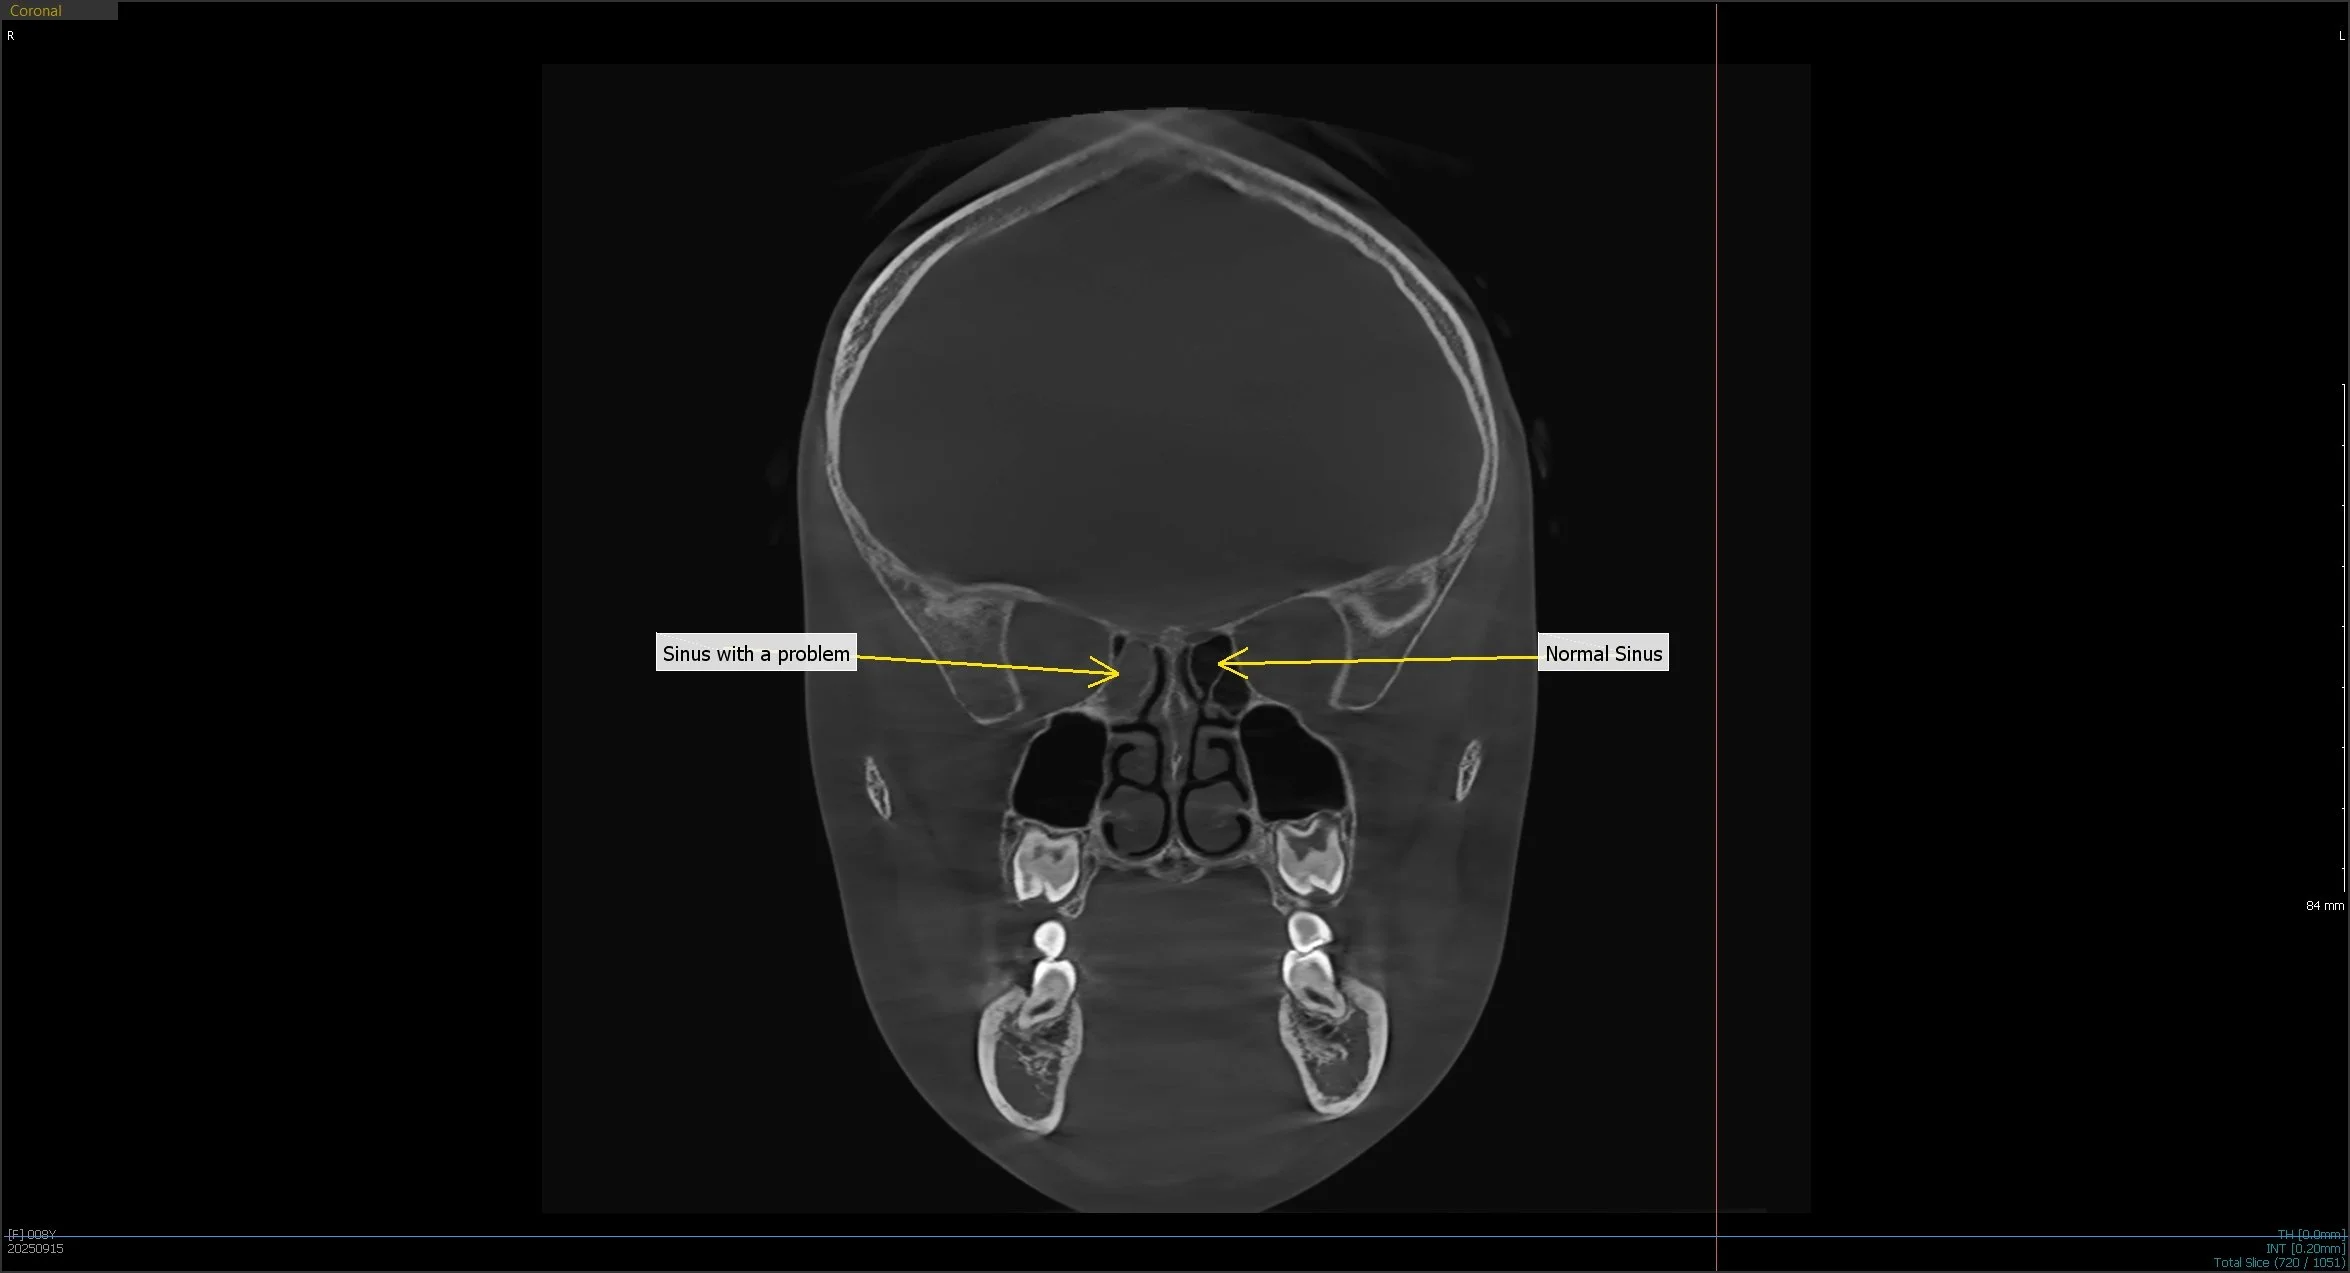

A medical scan showing a coronal view of a human skull with labels pointing to the sinus areas, one indicating a 'Normal Sinus' and the other pointing to a 'Sinus with a problem'.

Misaligned bites and underdeveloped jaws can have lifelong consequences if left unaddressed. Narrow dental arches, recessed jaws, and airway restrictions often contribute to sleep issues, teeth grinding, and poor facial balance. These conditions are not always visible during a routine exam, but 3D x-rays provide a full-volume view of the skeletal and airway structures that shape a child’s growth.

Dr. Peddicord relies on these scans to measure jaw position, identify airway blockages, and evaluate facial symmetry from multiple angles. This depth of information is critical in determining whether a child would benefit from orthotropic therapy, which focuses on guiding forward growth rather than relying on extractions or surgery. By combining 3D imaging with a clinical exam, Dr. Peddicord can make earlier, more accurate diagnoses that lead to better long-term outcomes.